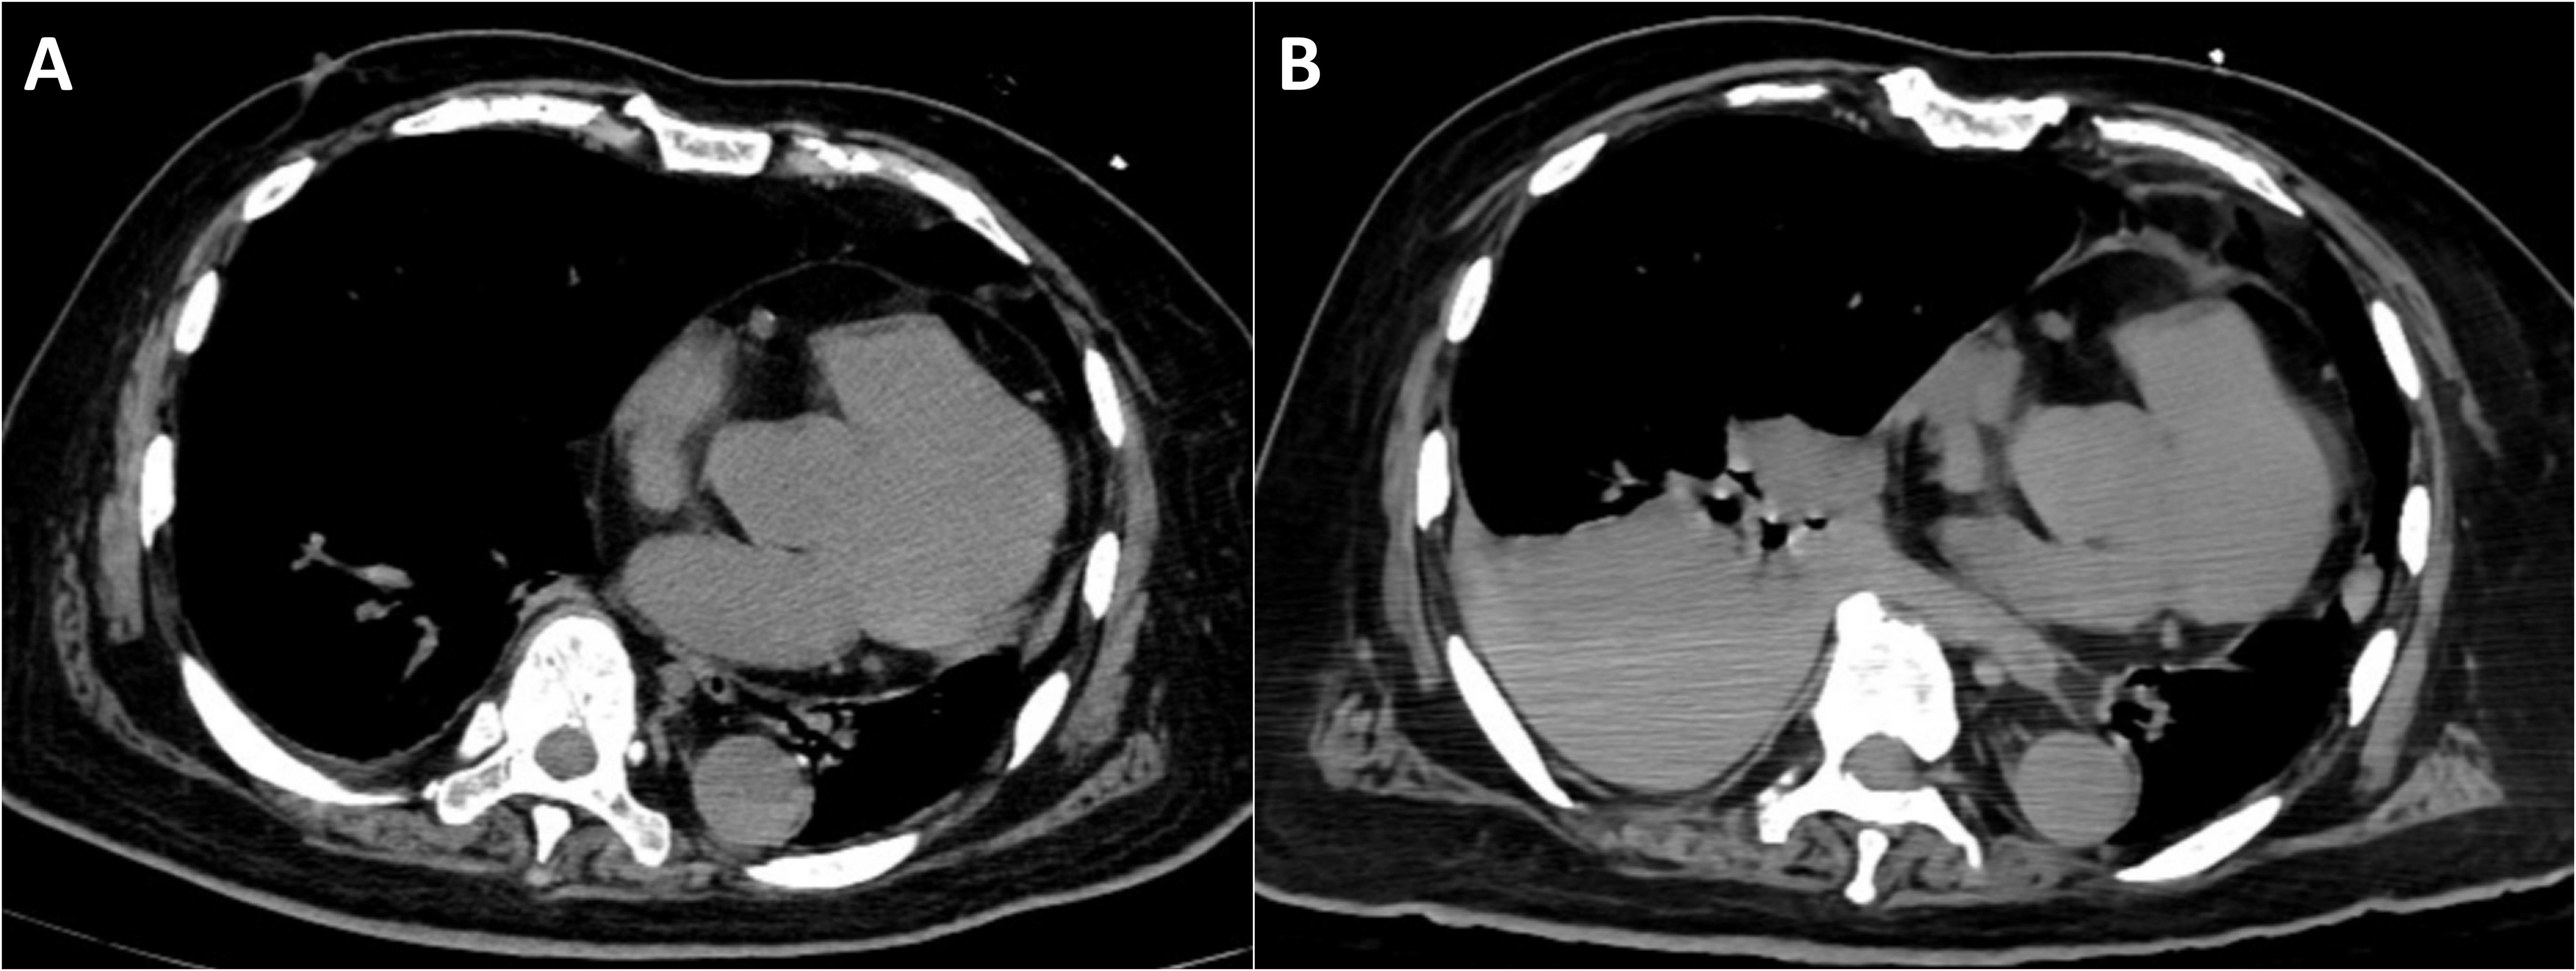

Background: Tumor lysis syndrome (TLS), characterized by electrolyte imbalances and acute kidney injury, predominantly occurs following cytotoxic chemotherapy in hematologic malignancies. Spontaneous TLS (STLS) in solid tumors remains rare. This report describes STLS induced by a diagnostic liver biopsy and reviews the literature on procedure-associated TLS. Case Presentation: An 84-year-old male presented with extensive hepatic metastases and markedly elevated tumor markers. Ultrasound-guided percutaneous liver biopsy confirmed the diagnosis of metastatic adenocarcinoma. Within 24 hours post-procedure, the patient developed acute respiratory failure, anuria, severe metabolic acidosis (pH 7.23), hyperkalemia (5.5 mmol/L), acute kidney injury (creatinine 299 μmol/L), hyperuricemia (716 μmol/L), and elevated lactate dehydrogenase (3953 U/L), fulfilling the diagnostic criteria for TLS. Concurrent hemothorax occurred. Continuous renal replacement therapy (CRRT) achieved rapid correction of metabolic derangements, with parameters returning to normal within seven days. Conclusion: Diagnostic liver biopsy can induce STLS in patients with high-burden solid tumors. Our systematic analysis reveals that minimally invasive procedures may precipitate TLS, emphasizing the importance of prophylactic measures, early recognition, and immediate CRRT initiation for optimal outcomes.